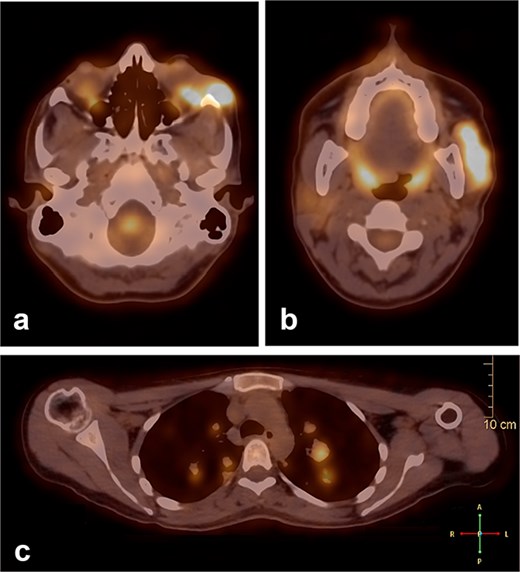

During follow-up, the patient complained of swelling at the left angle of the mandible and left lateral canthus. Orbit MRI showed local disease progression (Fig. 4). Ultrasonography of the left parotid region showed an irregular hypoechoic lesion in the left parotid gland. A PET scan revealed hypermetabolic malignant irregular soft tissue thickening within the lateral periorbital area of the left eye, consistent with a recurrence disease. Additionally, there is a new hypermetabolic irregular soft tissue mass in the left parotid gland with numerous bilateral scattered pulmonary nodules (Fig. 5). A biopsy from the left parotid gland confirmed the diagnosis of ACC, aligning with the primary tumor. The patient was diagnosed with lacrimal gland ACC with metastasis to the left parotid gland and the lungs. The Head and Neck multidisciplinary team proceeded with systemic chemotherapy using cisplatin and Navelbine. The patient started chemotherapy with good tolerance and clinical response and is now on regular follow-up with the oncology clinic.

A PET scan revealed hypermetabolic malignant irregular soft tissue thickening within the lateral periorbital side of the left eye (a), indicating a recurrence of ACC of the left eye, and a new hypermetabolic irregular soft tissue mass in the left parotid gland (b). Numerous bilateral scattered pulmonary nodules were noted (c).